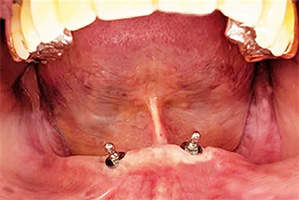

32年経過症例 / 91歳(2025年現在)・女性

1993年 下顎インプラント埋入時(59歳)